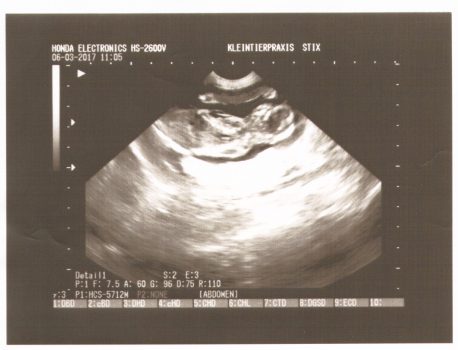

Wir waren beim TA zum Ultraschall und konnten mind. 4 Fruchtkammern mit Föten gut erkennen, sieht alles ok aus. Theoretisch hätten wir den Termin sparen können, mittlerweile sieht man ihr es schon an und der Appetit ist stark gestiegen. Aber wir haben bei der Gelegenheit noch einmal die Krallen kürzen …